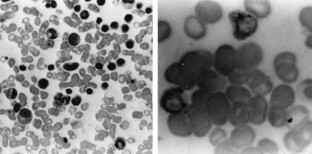

Magalhães, S., Duarte, F., Ribeiro, S. et al. Sideroblastic anemia following treatment of chronic myeloid leukemia with busulfan. Leukemia 14, 214–215 (2000). https://doi.org/10.1038/sj.leu.2401613